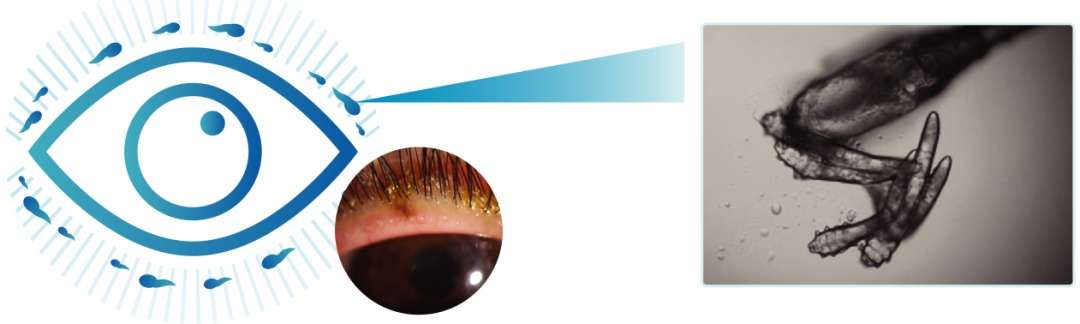

别觉得螨虫离你很远,它可是我们眼周的“常驻嘉宾”。这种叫蠕形螨的小虫子,个头只有0.1-0.4毫米,喜欢躲在睫毛毛囊和睑缘里,靠吃睑板腺分泌的油脂过日子,堪称“睫毛干饭人”。

很多人春天犯干眼,总以为是花粉过敏、长时间看手机,却忽略了这个“隐形元凶”。对此,湘潭爱尔仁和医院眼表综合科袁苑主任给出了专业解答“春日是眼部螨虫繁殖的高发期,也是螨虫相关性干眼的爆发期。当螨虫繁殖过剩,它们的排泄物、尸体不仅会堵塞睑板腺,导致睑板腺分泌的脂质质量异常,就像原本清亮的花生油变成了‘地沟油’,无法有效锁住泪液,进而引发蒸发型干眼,也就是临床常见的脂质异常型干眼。”